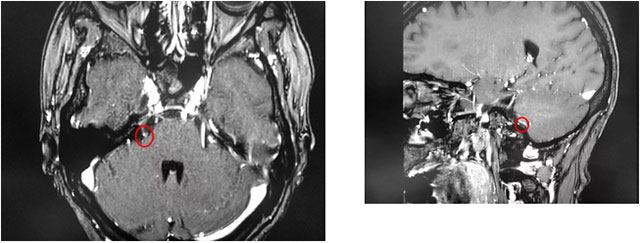

▲ 患者右侧三叉神经与周围小血管关系密切

最近,金女士慕名来到上海蓝十字脑科医院寻求进一步治疗。沈建康教授和医院神经外科6B病区潘仁龙主任团队结合患者病史和影像学分析,判断患者右侧三叉神经与周围小血管关系密切,经开展严谨的评估讨论并取得家属同意后,沈建康教授为金女士开展了微血管减压手术。